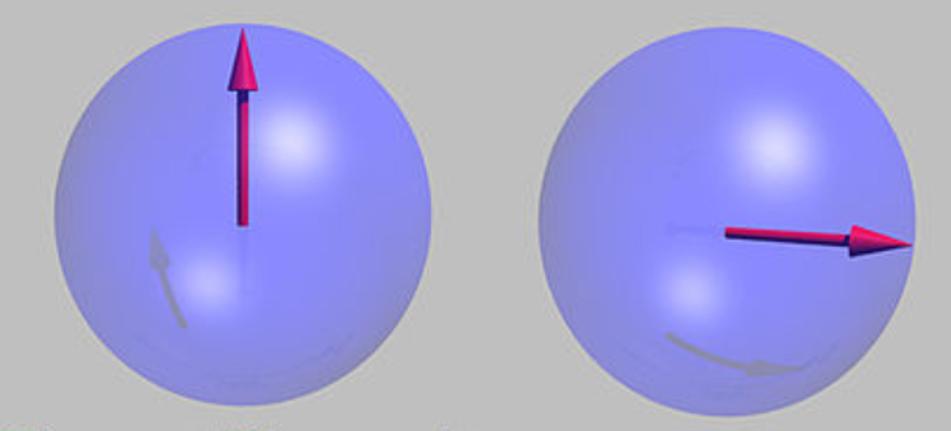

在外磁场作用下,质子自旋磁矩平行或反平行于外磁场

纵向磁场M和外加磁场同方向